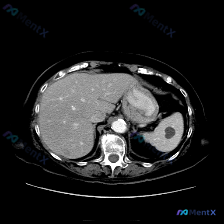

整理了一份很有意思的影像读片案例,一开始容易被提问带偏,仔细看下来其实是一个非常好的“临床思维”训练。 --- 病例基本情况 用户提出的问题是:“图像中描绘的具体异常是什么?脾脏病变”,附带了一幅腹部CT横断面(软组织窗)图像。 关键影像表现 我梳理了一下图像里的核心信息: 1. 脾脏:大小、形态正...

最近看到一个很有意思的影像分析场景,整理了一下思路和大家分享。 先看基础情况 用户预设了“脾脏病变”的方向,提供了一张腹部CT横断面软组织窗图像,从分析来看是增强扫描的动脉期或早期门脉期。 这张CT的核心表现 先整理一下明确的阳性/阴性信息: ✅ 图像质量:清晰度良好,无明显运动/金属伪影,软组织辨...